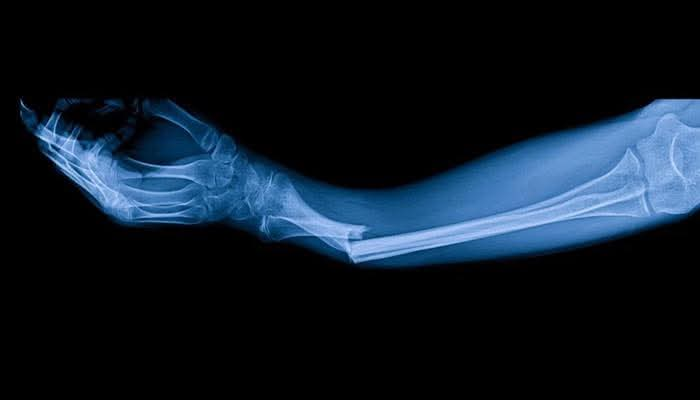

Chinese Scientists Develop ‘Magic Bone Glue’ That Heals Bones in 3 Minutes

Chinese researchers have created a breakthrough glue, named “Bone 2,” capable of repairing broken bones in just three minutes. Inspired by sea creatures’ natural adhesion, the glue bonds bones securely, absorbs into the body, reduces infection risk, and eliminates the need for additional surgery. Tested on over 150 patients successfully.